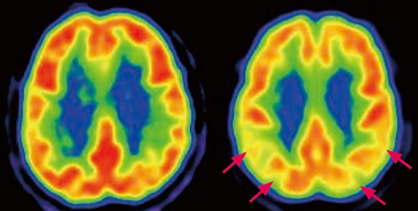

- MRI/CT: 뇌 위축 여부, 혈관성 치매 감별

- PET 검사: 베타아밀로이드 침착 여부 확인 (고비용)